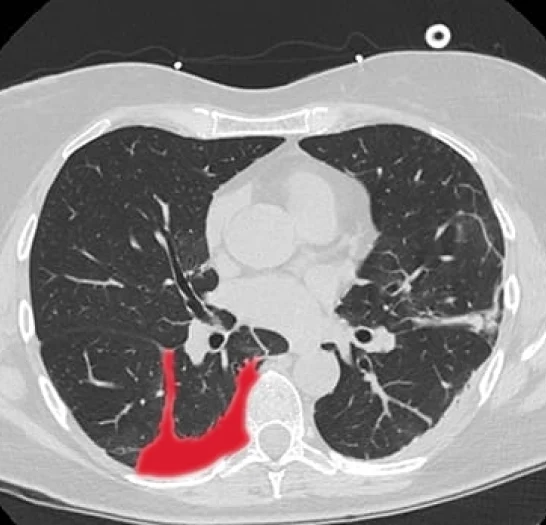

Pulmonology CT Annotation & Segmentation

Pareidolia Systems provides expert annotation and segmentation services for lung CT scans, supporting accurate AI-driven diagnosis of respiratory conditions. Our experts precisely delineate lung structures, nodules, consolidations, fibrosis, and vascular features, including critical pathologies like pneumothorax, lung tumors, emphysema, and infections. Every dataset undergoes rigorous clinical validation to ensure anatomical accuracy, disease-specific detail, and medical compliance. Our high-quality, annotated 3D CT datasets enable AI models to detect early lung diseases, quantify disease extent, and facilitate treatment planning for better patient outcomes.